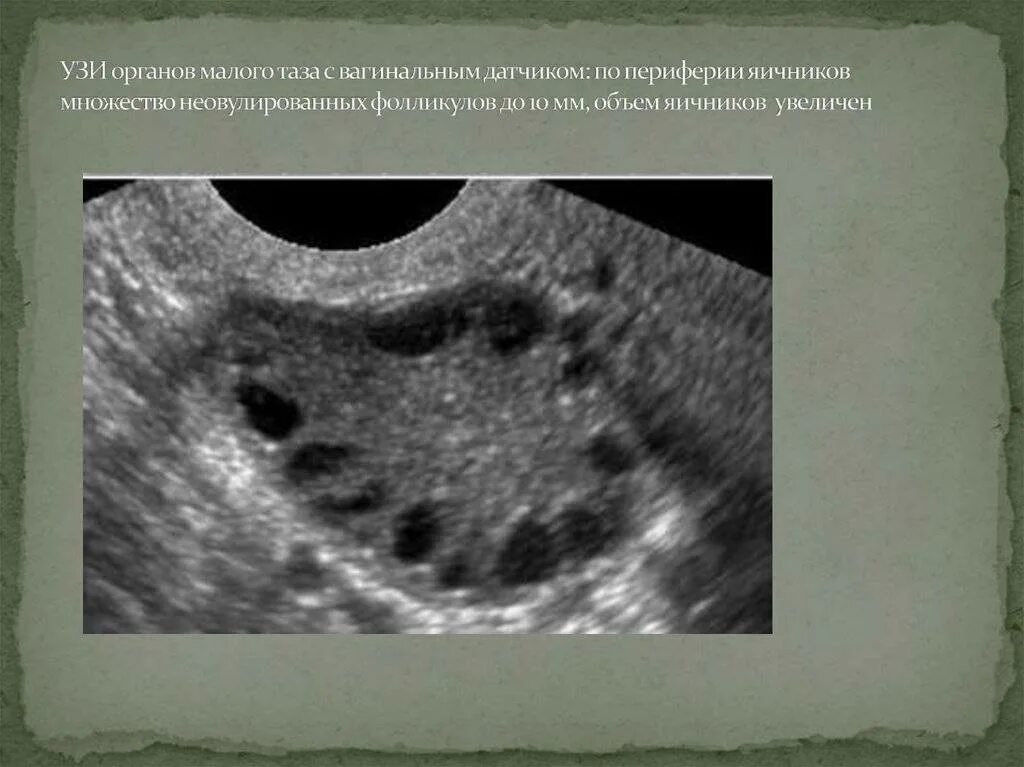

5 6 фолликулов в яичнике